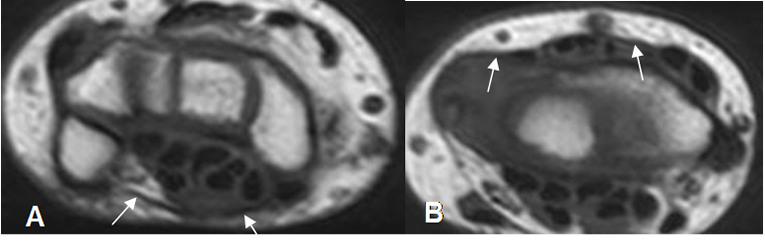

Con la RM se aprecian como imágenes hipointensas en todas las secuencias y mejor evaluados en vistas axial y sagital. (Fig 29, 30 y 31).

Fig 30. Mecanismo flexor normal.

A: RM sagital en T1. Inserción del flexor superficial en la base de la falange media (Flecha gruesa) y del flexor profundo, en la base de la falange distal (Flecha delgada).

B: RM axial en T2. Mecanismo flexor, fijado por las poleas en las falanges.

Fig 31. Músculos intrínsecos normales.

RM coronal en T1. Músculos lumbricales e interóseos normales.